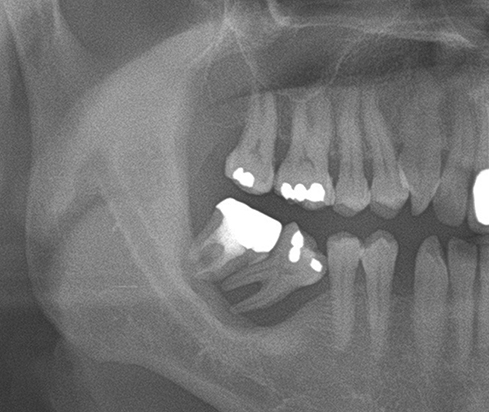

Another clinical case using non resorbable membrane and bone tac

• Another clinical case using  non resorbable membrane and bone tac 2